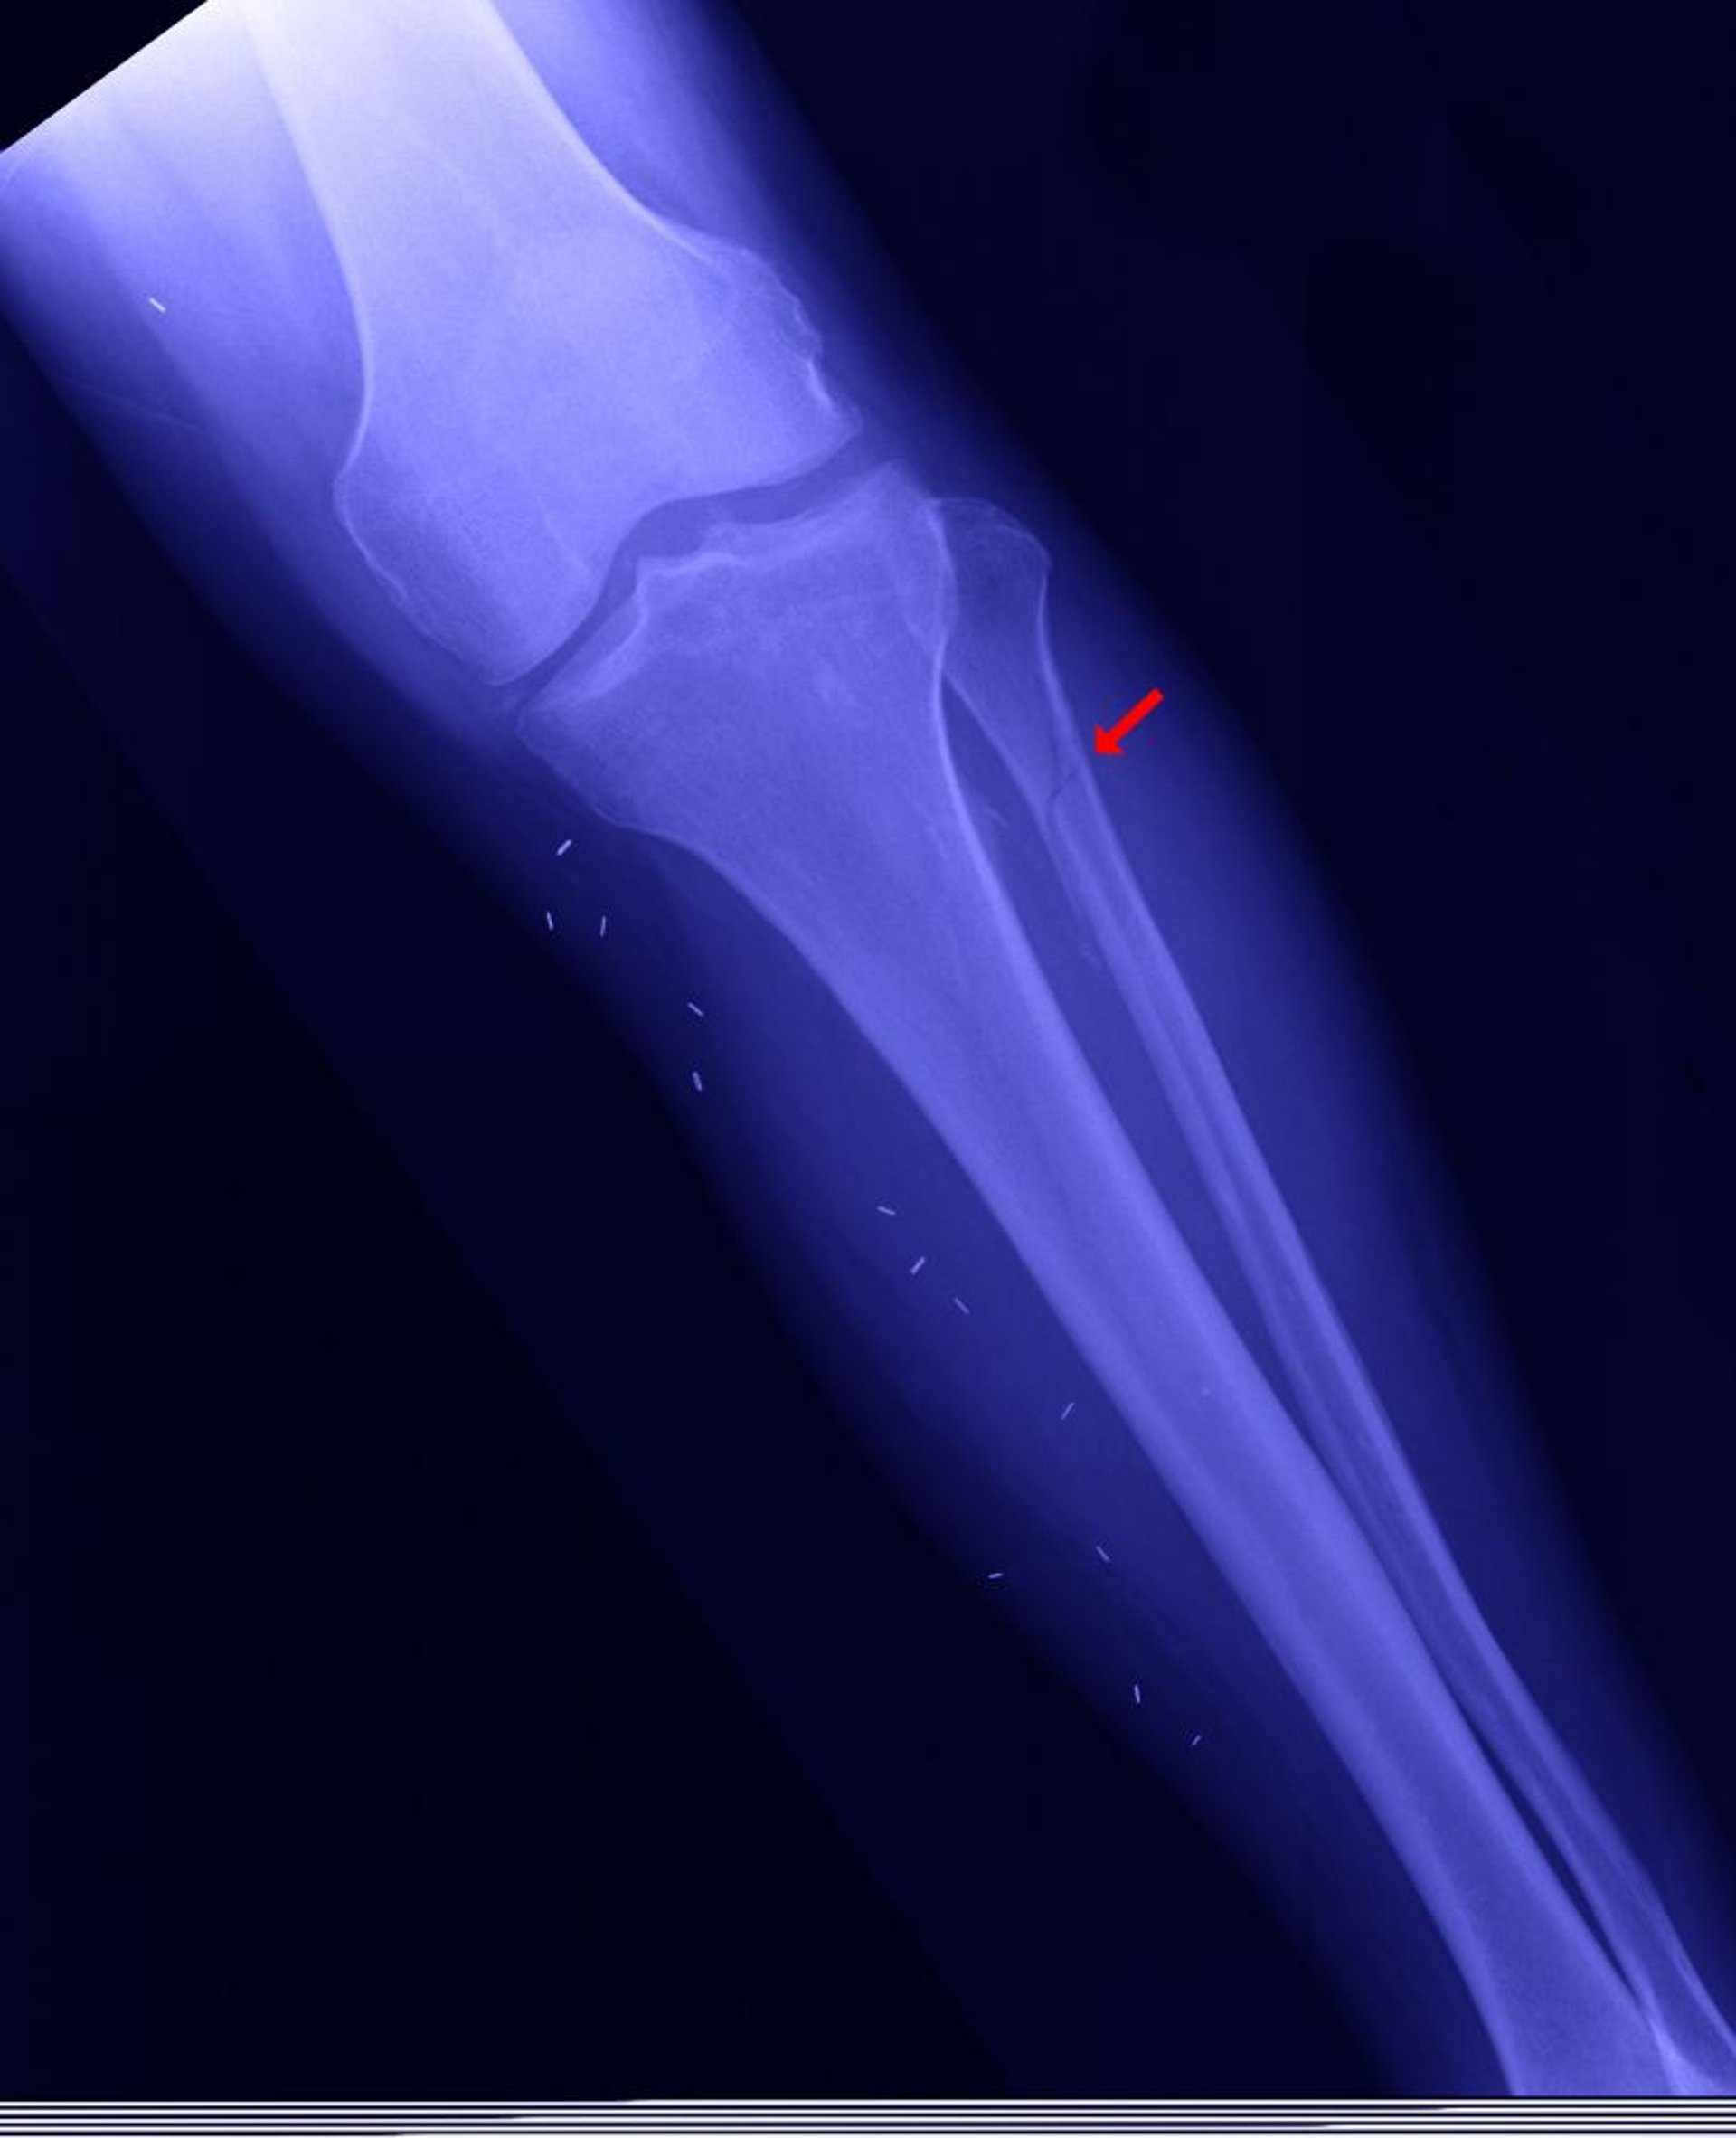

Proximale Fibulafraktur

Die proximale Fibula kann gebrochen werden (genannt Maisonneuve Fraktur - hier bezeichnet), wenn der Innenknöchel gebrochen ist, die Malleolengabel (die Verbindung zwischen Tibia und Talus) ist offen, und die distale Fibula ist nicht gebrochen.